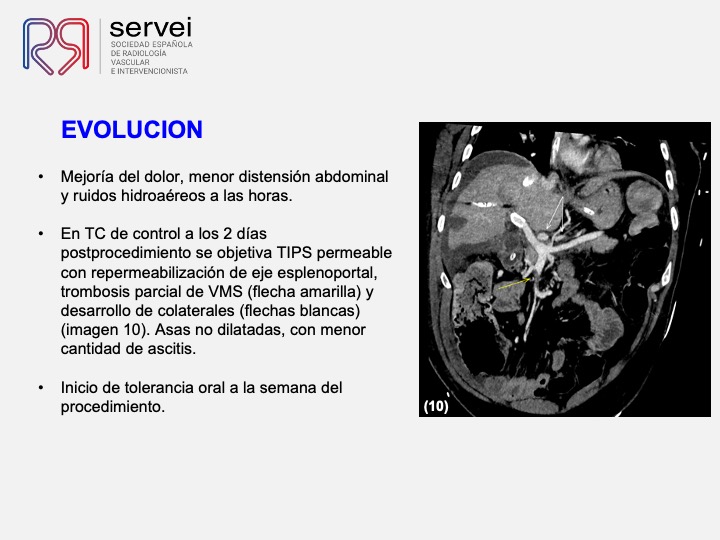

- Isquemia mesenterica venosa 01

- Isquemia mesenterica venosa 02

- Isquemia mesenterica venosa 03

- Isquemia mesenterica venosa 04

- Isquemia mesenterica venosa 05

- Isquemia mesenterica venosa 06

- Isquemia mesenterica venosa 07

- Isquemia mesenterica venosa 08

- Isquemia mesenterica venosa 09

- Isquemia mesenterica venosa 10

- Isquemia mesenterica venosa 11